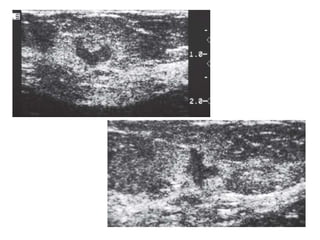

This patient presented with a mass on the mammogram at screening, which was assigned as BI-

RADS 0 (needs additional imaging evaluation).

Additional ultrasound demonstrated that the mass was caused by an intramammary lymph node.

The final assessment is BI-RADS 2 (benign finding).